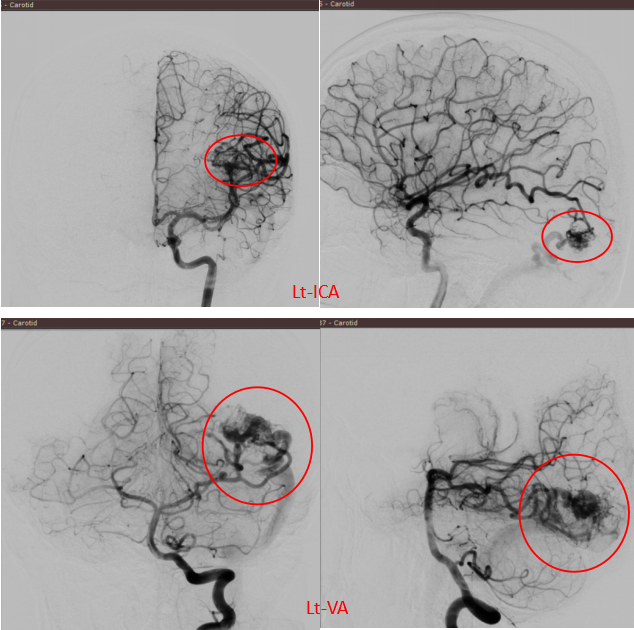

病情危急,必须尽快明确诊断并制定治疗方案。医疗团队立即为艾力进行了全脑血管造影(DSA),清晰显示出畸形血管的供血动脉、内部结构(血管构筑)和引流静脉。

全脑血管造影(DSA)是诊断脑血管疾病的「金标准」。